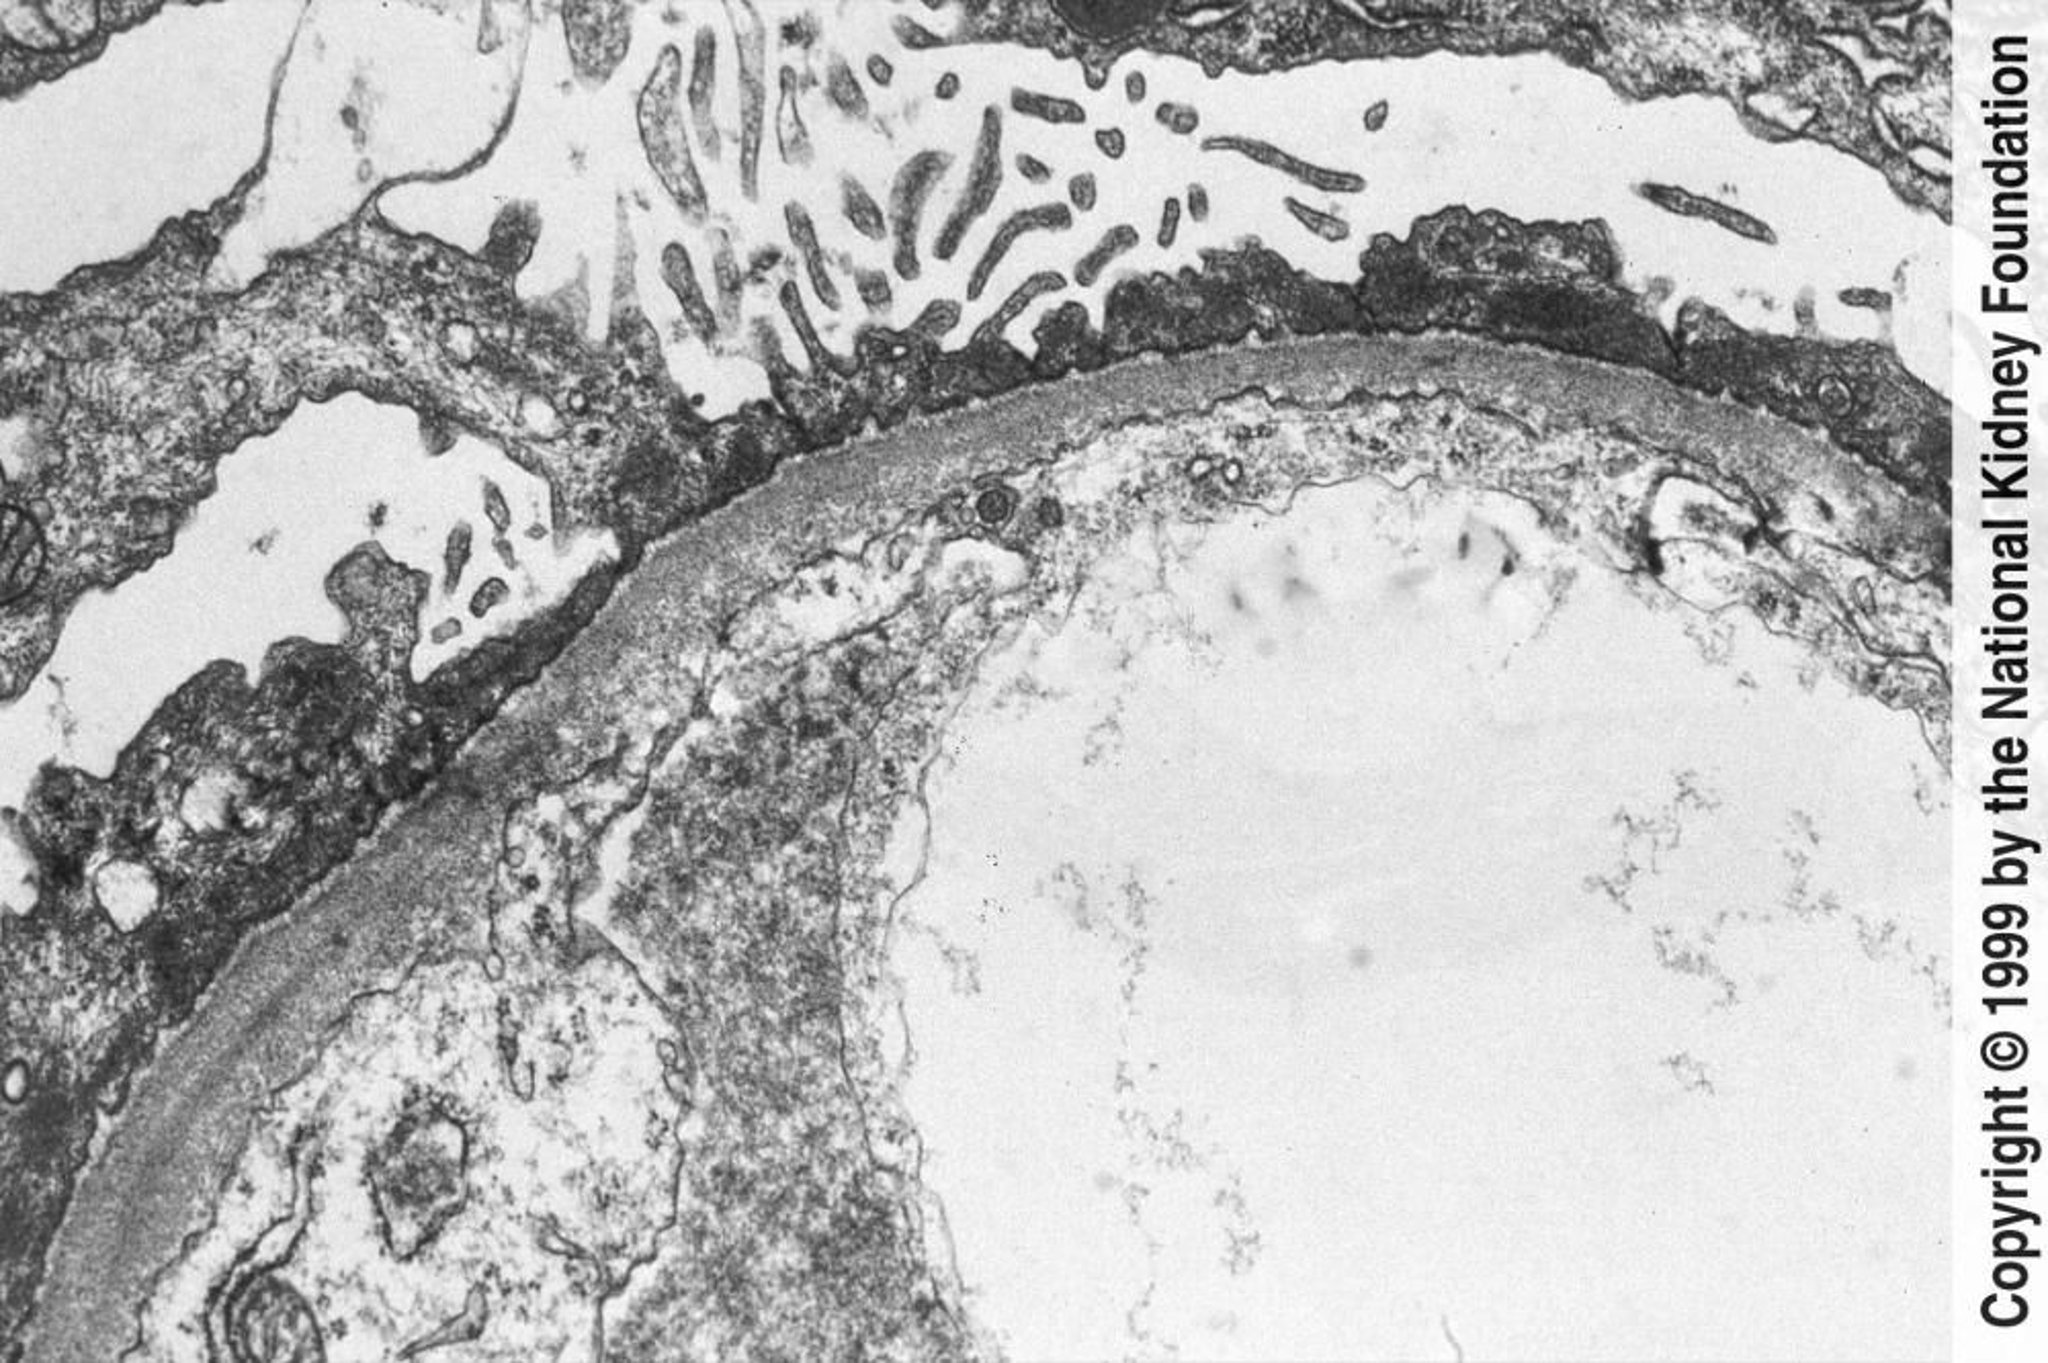

Maladie à lésions minimes

Un effacement diffus des pédicelles peut être observé en microscopie électronique à transmission (×800).

Image fournie par Agnes Fogo, MD, and the American Journal of Kidney Diseases' Atlas of Renal Pathology (voir www.ajkd.org).